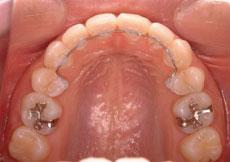

症例: 施術前・施術後

施術前

施術後

上下が前方に出ている状態でしたので、上下左右の第一小臼歯、計4本を

抜歯

して治療を行いました。

治療前の状態

上下が前方に出ている上下顎前突と、前歯を中心とする歯のデコボコ、そして右下の奥歯が内側に傾いている状態でした。

治療

口元の突出感をすごく気にされていたので、

での治療を行いました。

治療後は、口元もすっきり整い奥歯の傾きも治り、咬み合わせも良好になりました。